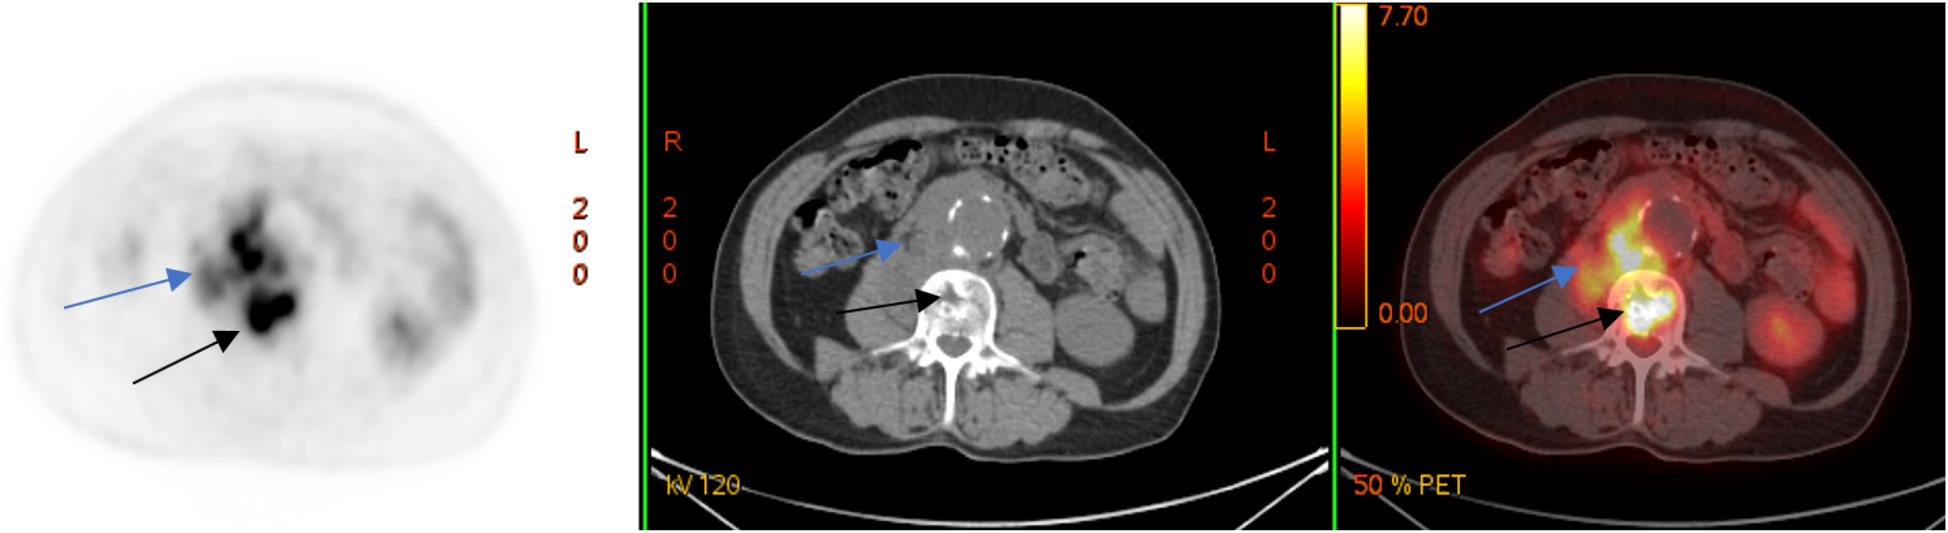

A laboratory examination on 12 March 2024 showed elevated levels of C-reactive protein (CRP, 26.62 mg/L) and leukocytes 6.4 × 109/L. To clarify the diagnosis, a couple of days later, the patient underwent positron emission tomography combined with computed tomography (PET/CT) with the use of 18F-fluorodeoxyglucose (18F-FDG), which revealed a metabolically active retroperitoneal infiltrate extending to the right psoas muscle and the L2–L3 vertebral bodies (Figure 2).

Figure 2

18F-FDG PET/CT (axial slices) demonstrates the presence of a metabolically active retroperitoneal infiltrate with extension to the right m. psoas (blue arrows) and lumbar vertebral bodies (black arrows).